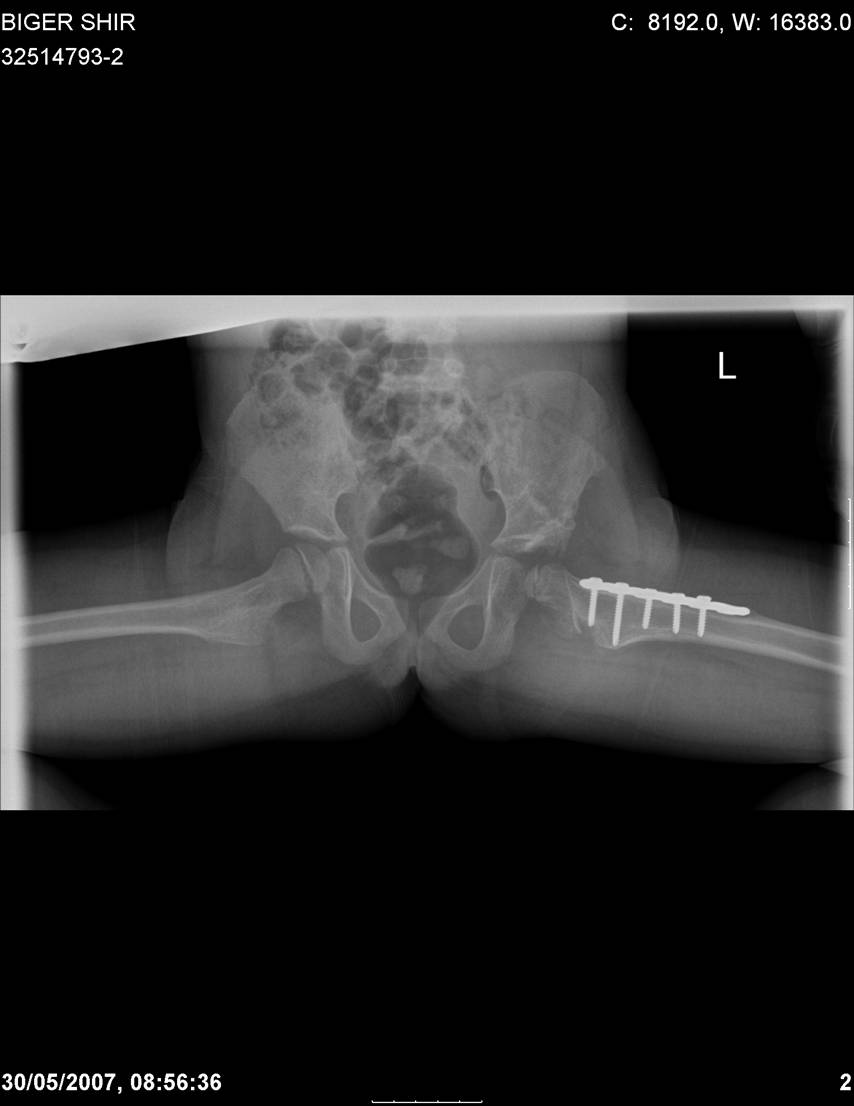

Chto by ne byt goloslovnym posilau vam svoi sluchai gde sdelal vse chto napisal vyshe